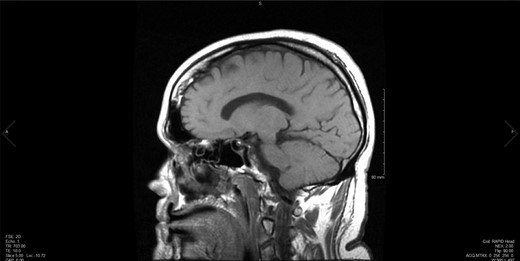

Upon the unimpressive decrease in HbA1C despite an appropriate increase in medical therapy, Cushing’s syndrome was suspected and diagnostic work up was pursued (Fig. 1). A dexamethasone suppression test as well as a late night salivary cortisol test showed abnormal results. The late night cortisol test showed high values congruent with the range necessary for diagnosis of Cushing’s syndrome (>7.5 mcg/dl) [3]. These findings were suggestive of ACTH-dependent Cushing’s syndrome. At this point, an MRI of the brain with sella protocol was ordered and showed no evidence of a pituitary adenoma or pituitary etiology (Fig. 2). Bilateral inferior petrosal sinus sampling was performed (IPSS) and the results were highly suspicious for pituitary microadenoma located more on the left side of the gland, with some activity also present on the right side (Fig. 3). The peak IPSS ACTH value was 1031 pg/ml. A repeat MRI of the brain with sella protocol with higher resolution (3 T MRI with sella protocol with thin cuts) was done in order to visualize the lesion for surgical planning, which did not show any pituitary lesion. FSH, LH, prolactin, insulin-like GF-1, TSH, free T4 and testosterone labs were ordered, and all were within normal limits.